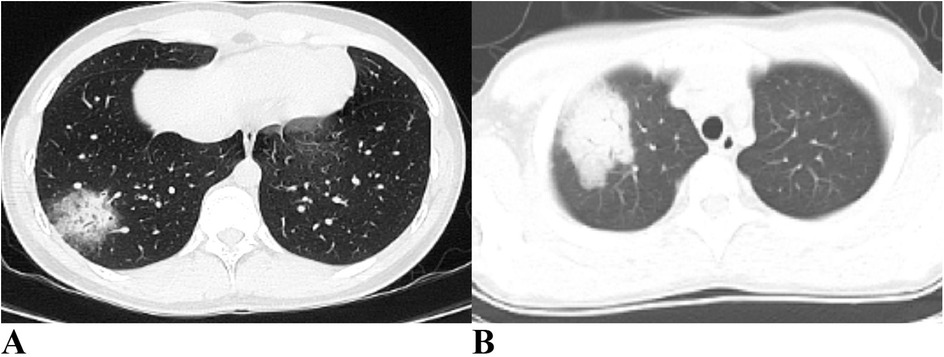

As shown in Table 4, approximately half of the pediatric patients exhibited involvement of two or more lung lobes. Lung imaging findings frequently include the halo sign, bronchial inflation sign, or consolidation (Figure 4). Flexible bronchoscopy revealed bronchial mucositis with flocculent secretions in the examined patients (Figure 5A). Cytological analysis of BAL fluid revealed a predominance of neutrophils, followed by monocytes and alveolar macrophages (Figure 5B).

Figure 4

Panel A shows: Halo sign and air bronchogram sign are evident in the right lung. Panel B shows: Consolidation is observed in the right lung.

Figure 4. Ct imaging features of the lungs in children with CPP. (A) Halo sign and air bronchogram sign are evident in the right lung. (B) Consolidation is observed in the right lung. CPP, Chlamydia pneumoniae pneumonia.

Lung imaging characteristics in children with CPP are often nonspecific. Previous studies have indicated that more than half of pediatric patients present with unilateral pneumonia, and a minority show bilateral lung involvement (16, 17). Subpleural masses with high-density shadows accompanied by peripheral halo signs may have diagnostic value, as observed in 60% of cases (6/10) in one study (16). Air bronchogram signs were present in 70% (7/10), whereas pulmonary embolism was noted in 20% (2/10) of the children with CPP (16). A small proportion also exhibited patchy pulmonary consolidation (16). In our study, over half of the patients had involvement of two or more lung lobes, with some showing halo signs, air bronchogram signs, or pulmonary consolidation. Consistent with previous reports, no pathognomonic imaging features specific to CPP were identified.